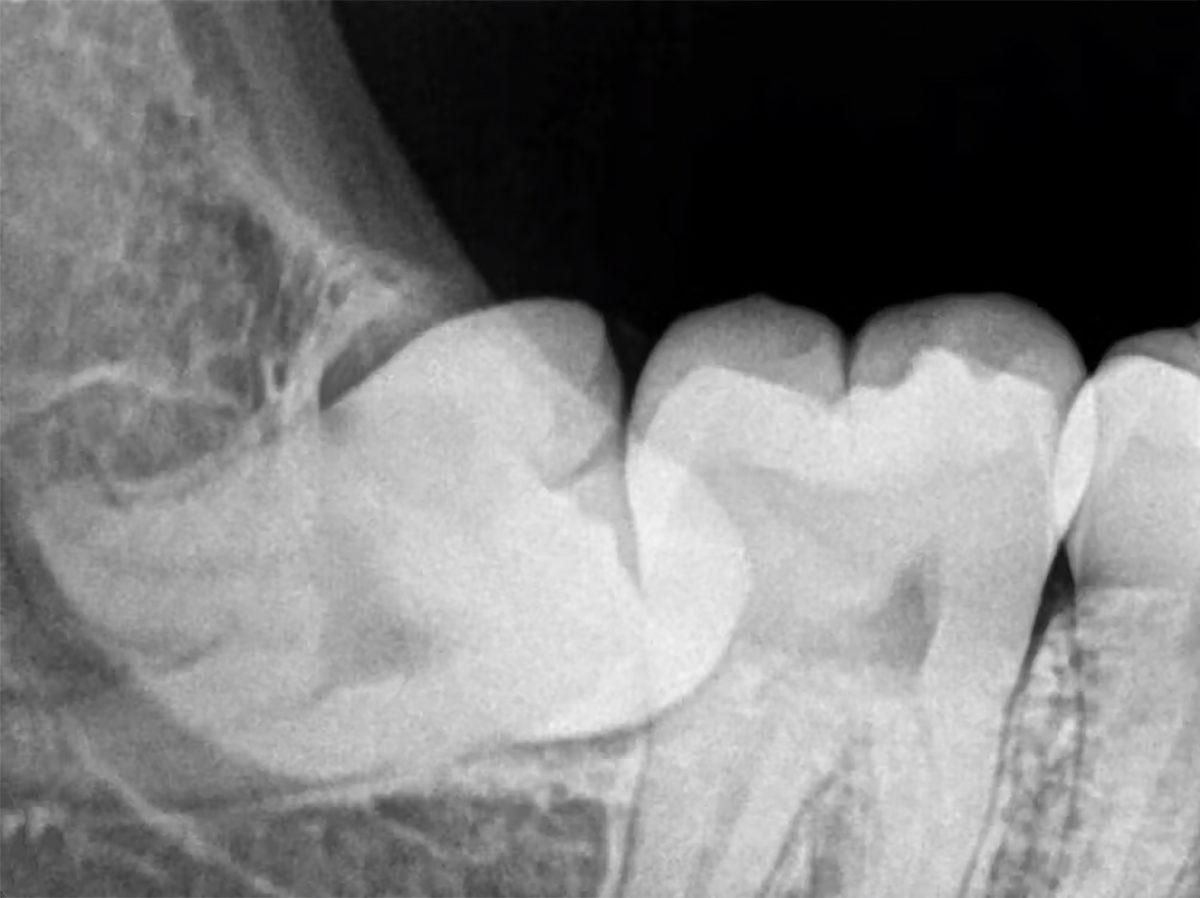

Yazıyı okurken acıları aklına gelenler olabilir. Çünkü 20’lik dişin çıkma süreci kimilerinde ağrıya neden olabiliyor. Çoğu zaman yeterli alan olmadığı için dişler yan yatmış şekilde çıkabiliyor veya tamamen çıkamayarak gömülü kalabiliyor.

Bu durumlar da çevre dişlere baskı yaparak ağrı, enfeksiyon ve diğer dişlerin düzensiz yerleşmesine sebebiyet veriyor. Tüm bu nedenler de 20’lik diş çektirmeye kadar gidiyor. Eğer hayatı olumsuz yönde etkiliyor ve enfeksiyon, ağrı gibi nedenlerin yanı sıra başka sorunlar da teşkil ediyorsa diş hekimi tavsiyesi ile 20’lik dişlerin çekilmesi gerekebiliyor.